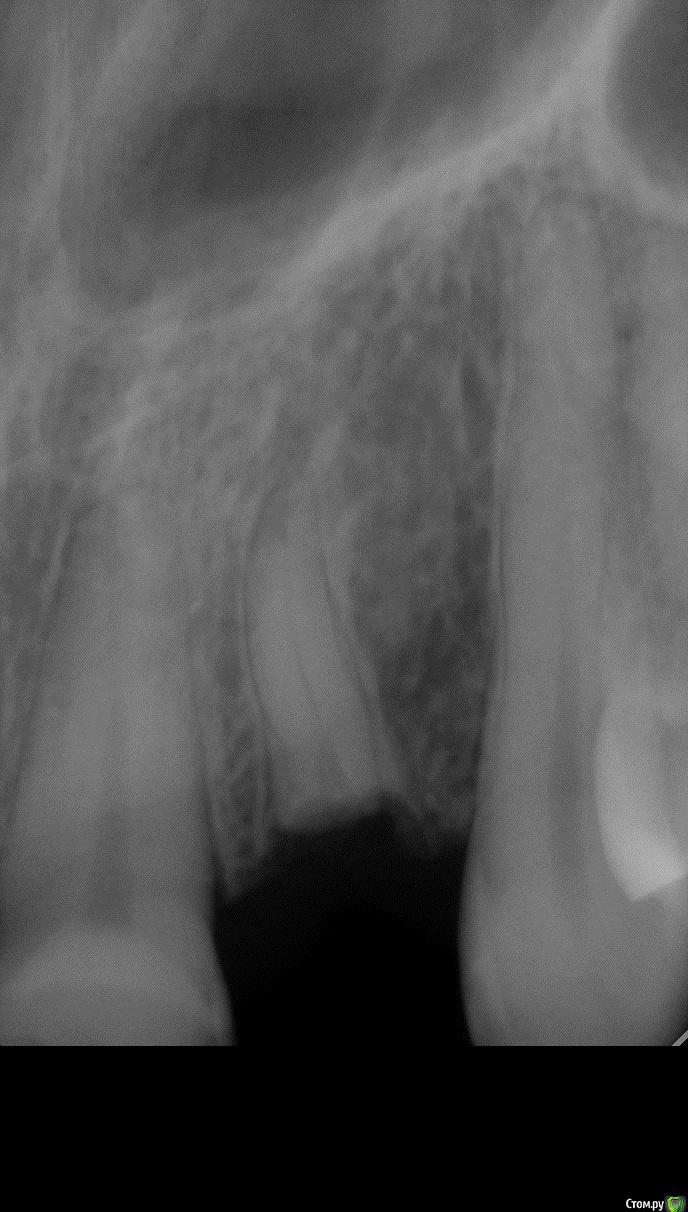

Sundance Опубликовано 10 июня, 2015 Автор Поделиться Опубликовано 10 июня, 2015 как удаляли, периотомом связку то рвем?да но на корне остаются места со связкой и чем их больше тем больше шансов что будет полное востановление приодонта , правда в етом случаи другая ситуация корень уходил под кость на 2 мм пришлось на недельку поставить ортодонтическую тягу и только после етого удалять Ссылка на комментарий

Sundance Опубликовано 10 июня, 2015 Автор Поделиться Опубликовано 10 июня, 2015 Тогда зачем удалять, если можно вытянуть?результат почти одинаковій но здесь у корня еще дефект дистально нада было ево повернуть + так еще быстрее Ссылка на комментарий

Sundance Опубликовано 10 июня, 2015 Автор Поделиться Опубликовано 10 июня, 2015 И сколько по времени? при хирургической екструзии через 3 недели после удаления можно нагружать Ссылка на комментарий